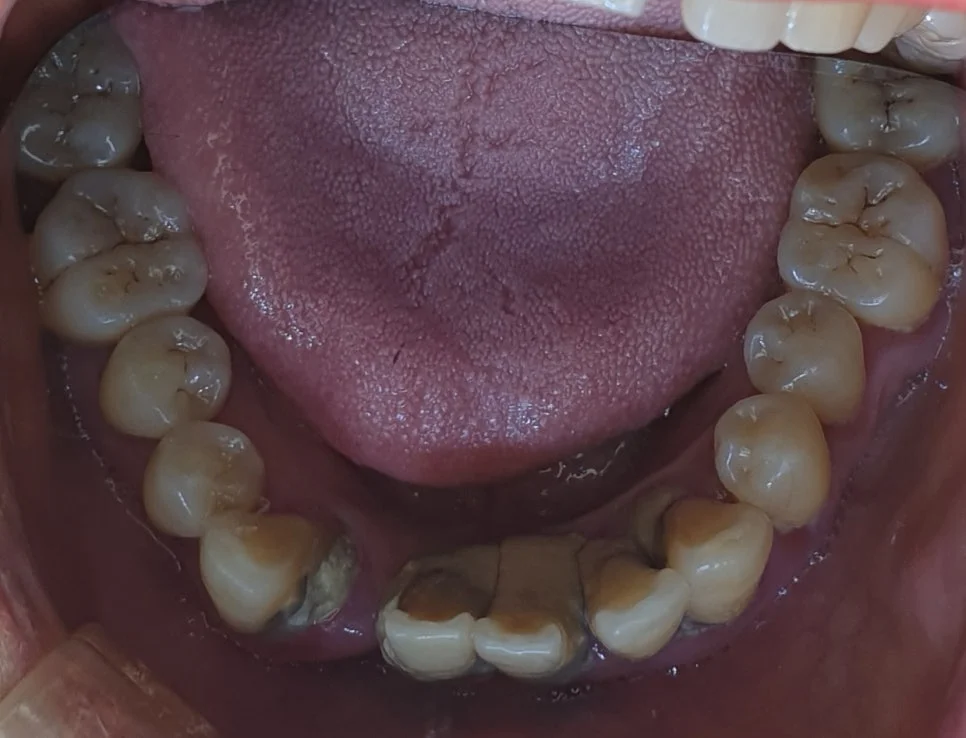

치료 전 (Before)

어금니를 조기에 상실하게 되면 상대적으로 앞니가 많은 힘을 받게 되고, 이로 인해 앞니가 버티지 못하고 흔들리게 되는 경우가 많습니다ㅜ

많은 치석과 치조골의 소실로 대부분의 치아를 발치해야 하며 임플란트 식립이 필요합니다. 보통 많은 치아의 발치 및 임플란트가 계획된 경우 위아래 두 번에 걸쳐 임플란트를 식립하게 됩니다.